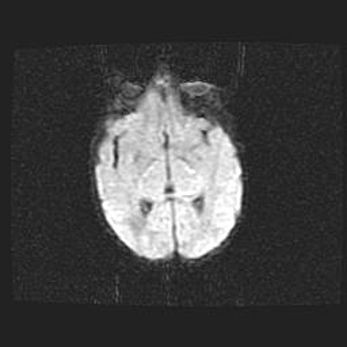

Церебральная ишемия II.

Возраст: 5 дней

Вес: 3400 г

Пол: женский

Окружность головы: 35 см

Срок гестации: 39 недель

Церебральная ишемия – это заболевание, характеризующееся недостаточностью (гипоксией) либо полным прекращением (аноксией) снабжения мозга кислородом по причине закупорки одного или нескольких сосудов. Это приводит к  что метаболическим расстройствам различной степени тяжести в тканях головного мозга, развитию коагуляционных некрозов и гибели нейронов.